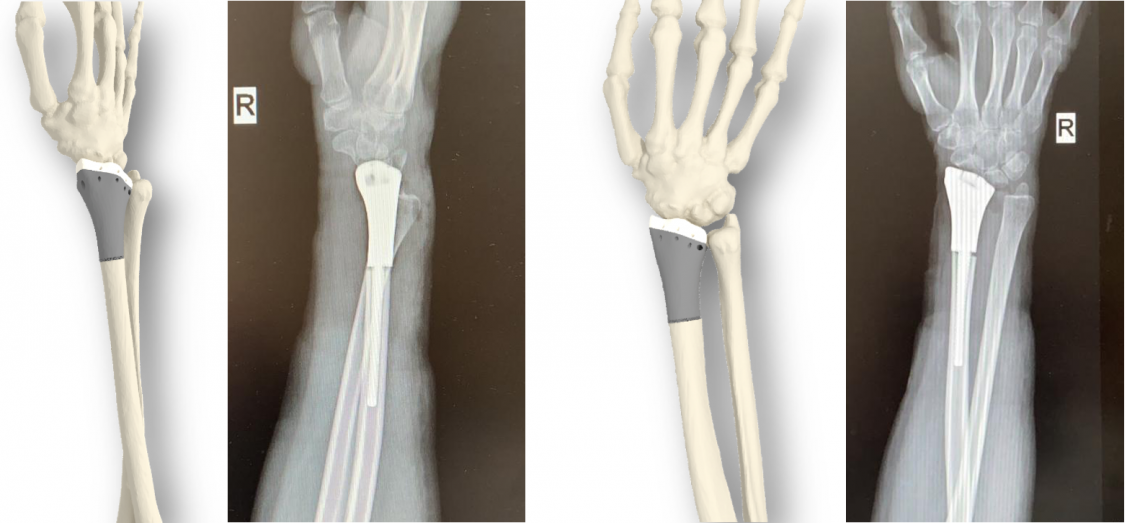

Резидент столичного технопарка «Калибр» — «Инновационно-технологическая компания Эндопринт» — запатентовал новый однополярный эндопротез лучезапястного сустава. Разработка позволяет заместить пораженную область кости и сустава и сохранить при этом полную подвижность кисти руки. Изделие проектируются с учетом индивидуальных особенностей сустава и каналов кости конкретного пациента и печатаются на специальном 3D-принтере из титана.

Биоинженеры «ИТК Эндопринт» разработали способ создания индивидуальных эндопротезов, учитывающих анатомические особенности пациента, на основе снимков его компьютерной томографии. При этом учитывается необходимость обеспечения комфорта и полной подвижности сразу после завершения реабилитации. Прошедшие стадию проектирования и одобренные врачом имплантаты изготавливаются из титана методом 3D-печати на высокоточном принтере.

Разработанная компанией система эндопротезирования лучевой кости уже применяется в онкологии, травматологии и ортопедии. Она дает возможность провести замещение пораженных участков и сохранить все здоровые ткани. Тело имплантата повторяет форму здоровой кости и имеет пористый штифт, соответствующий особенностям строения суставов именно этого пациента. Штифт устанавливается при помощи специально разработанного для этой цели инструмента, который сокращает время операции. Благодаря такому способу введения для фиксации не требуется использовать винты, а пористая конструкция дает возможность костным структурам со временем «врасти» в имплантат, делая его одним целым с костью. Кроме того, разработчики создали специальный вкладыш из хирургического полиэтилена, который точно повторяет хрящевую поверхность и исключает истирание хряща, давая суставу возможность стабильно вращаться. Предусмотренные во вкладыше отверстия для фиксации связок участвуют в сохранении стабильности сустава после эндопротезирования. Также частью системы являются примерочные модели, которые позволяют врачу заранее спланировать операцию и детально к ней подготовиться.